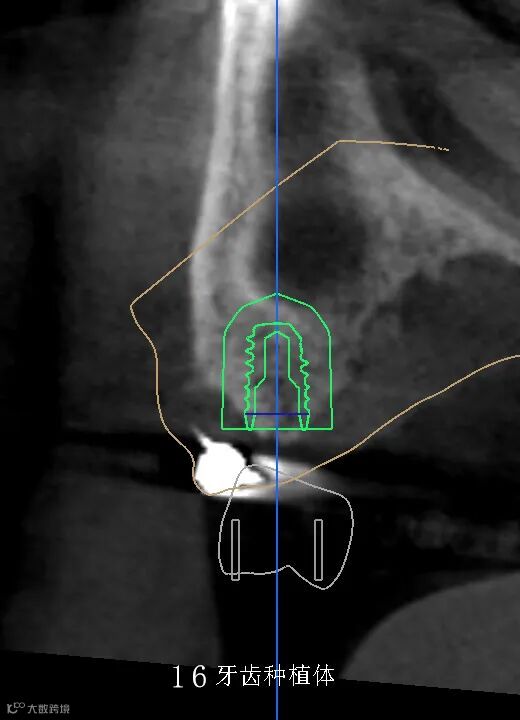

数字化种植手术规划与导板设计

临床种植手术过程